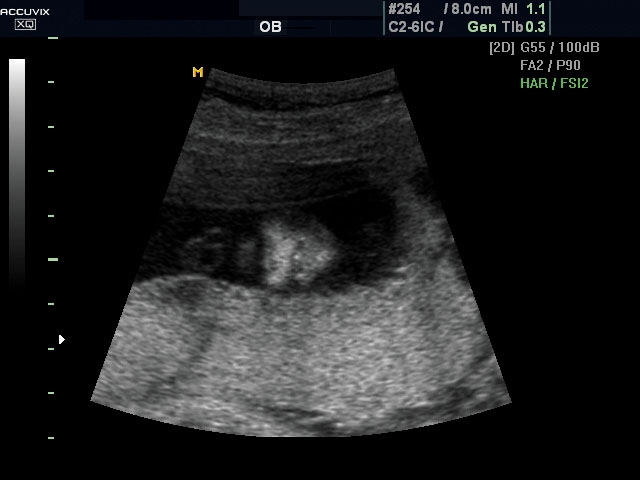

A pontos analízis és diagnózis iránti egyre növekvő igény kiszolgálására a MEDISON egy új real time képfeldolgozó technológiát fejlesztett ki Dynamic MR™ elnevezéssel. Az eljárás a diagnosztikus ismeretanyagot a precizitás és a pontosság egy teljesen új szintjére emeli. Használata az alapvető 2D ultrahang képinformáció real time, kivételesen kristálytiszta és kiemelkedően részletezett megjelenítését teszi lehetővé tűéles kontúrok és finoman rajzolt szövetstruktúra mellett. A DMR™ technológia ideális eszköze az ultrahang-diagnosztikának kezdve a szülészet-nőgyógyászattól a foetalis echon át az általános alkalmazásokig.

A DynamicMR alkalmazása az átlagos ultrahang teljesítményt a zaj és szemcsézettség jellegű műtermékek kiszűrése révén a vizuális diagnosztika, a precizitás és a pontosság új szférájába emeli. Figyelje meg a cerebellum, CSP és cisterna magna élstruktúráit, mennyire pontosan definiáltak és a teljes agyi struktúra ábrázolása a Dynamic MR alkalmazásával milyen látványosan javul.